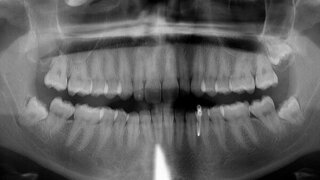

MKG-ChirurgieFollikuläre Zyste in der Kieferhöhle infraorbital – mit Hypästhesie Bei einer Hypästhesie des Nervus infraorbitalis nV2 sind Überraschungen durchaus möglich, wie der Patientenfall zeigt. 29.01.2021 ZahnmedizinChirurgie